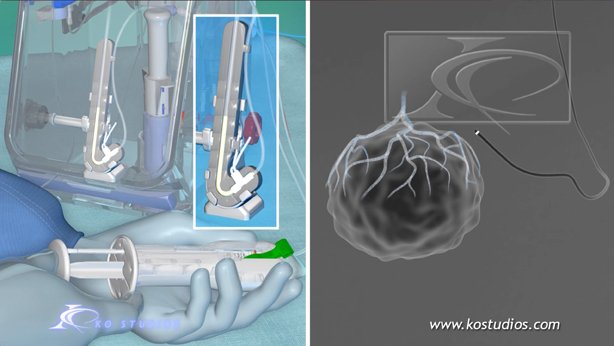

EnCompass F2 Device for cerebral embolic protection system in TAVR procedures

EnCompass Technologies

EnCompass’ F2 filter has pores small enough to block most emboli to the brain while preserving blood flow. During the TAVR procedure, 360-degree wall apposition of the filter in the aortic arch prevents migration. The filter, attached to a self-expanding, nitinol stent, is easy to insert, deploy and retrieve, according to the company. Copyright ©2021 KO Studios.